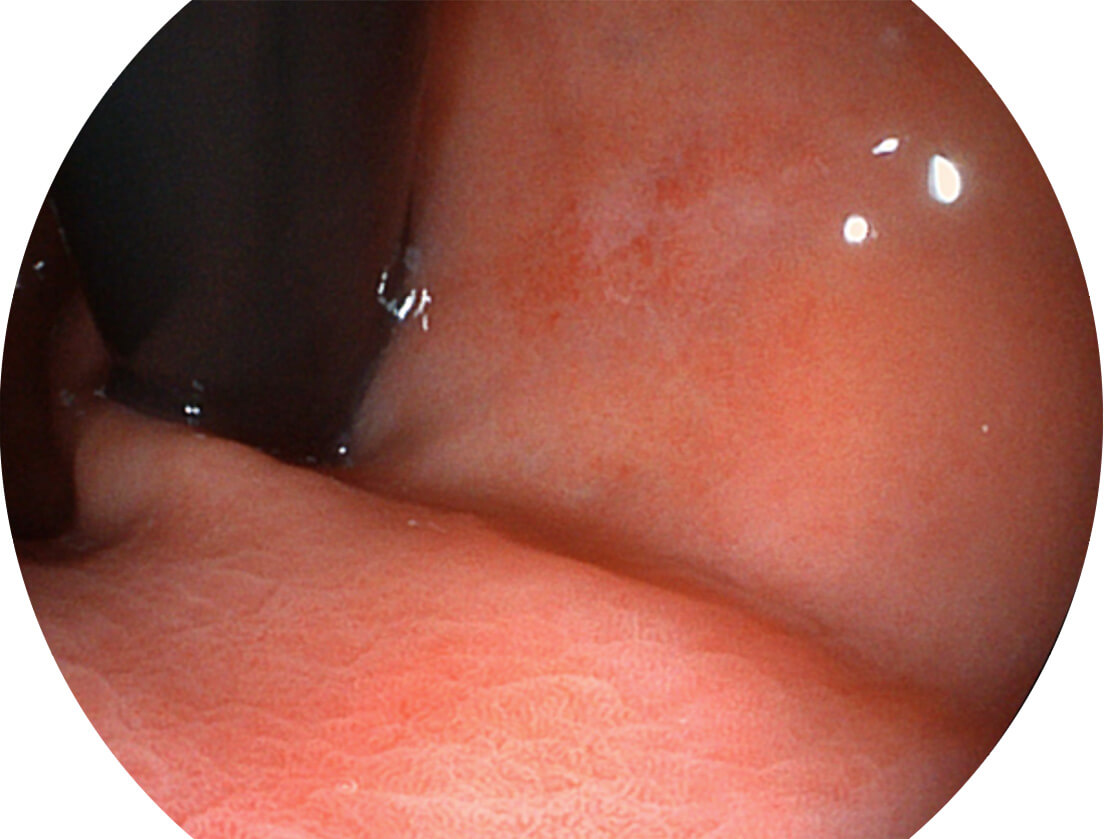

强调浅层黏膜结构的同时,保证照明亮度和提升浅层微血管与中层血管颜色对比度,病变边界更清晰。

VIST图像